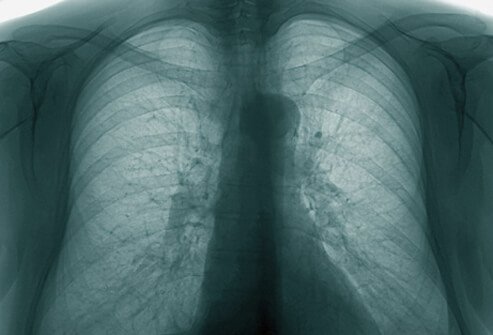

Sebuah rontgen pada dada, mengambil gambar dari jantung, paru, pembuluh darah, saluran pernafasan, dan kelenjar getah bening di daerah ini. Tulang dada, tulang rusuk, dan tulang selangka juga masuk dalam gambar. Gambar ini juga menunjukkan bagian atas tulang belakang. Rontgen dada digunakan untuk mendiagnosis masalah kesehatan yang menimbulkan gejala di daerah dada seperti masalah paru dan pernafasan serta gangguan jantung. Pada kebanyakan kasus, rontgen dada melibatkan dua gambar, yaitu gambar yang diambil dari belakang, dan satu lagi diambil dari samping.